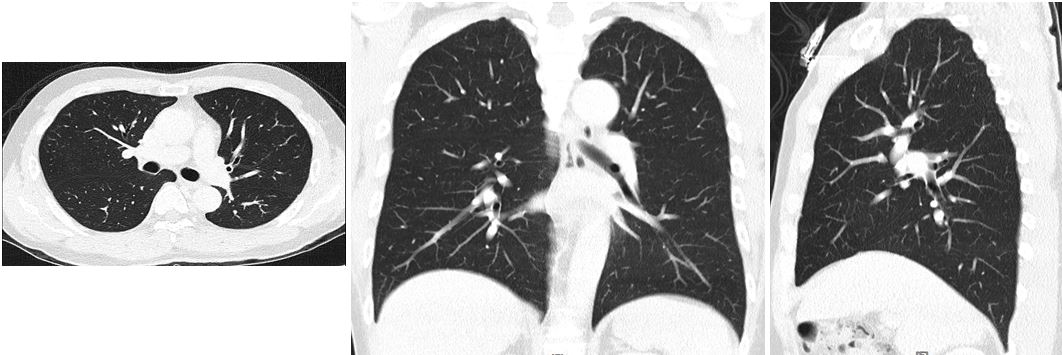

2. 低劑量肺部電腦斷層檢查(LDCT: low-dose computed tomography)

低劑量電腦斷層肺部檢查為使用切片厚度<1mm的新型多排偵檢器的電腦斷層掃描儀,可在閉氣約數秒鐘快速完成肺部的掃描,使用的輻射劑量遠低於電腦斷層肺部掃描低。

利用三維的肺部影像處理,同時使用橫切面、矢切面及冠狀切面影像評估肺部,可偵測出小於0.5cm的肺部結節,達到早期診斷及早期治療的目的。

建議受檢對象:

- 40歲以上者

- 長期吸菸及常處於二手菸環境者

- 有肺癌家族史的肺癌高危險群

- 經常接觸油煙、粉塵及化學物質者